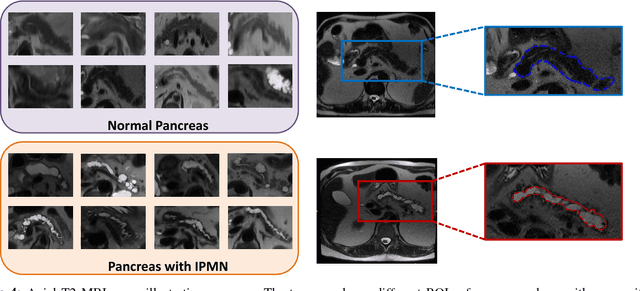

Abstract:Pancreatic cancer is projected to become the second-deadliest malignancy in Western countries by 2030, highlighting the urgent need for better early detection. Intraductal papillary mucinous neoplasms (IPMNs), key precursors to pancreatic cancer, are challenging to assess with current guidelines, often leading to unnecessary surgeries or missed malignancies. We present Cyst-X, an AI framework that predicts IPMN malignancy using multicenter MRI data, leveraging MRI's superior soft tissue contrast over CT. Trained on 723 T1- and 738 T2-weighted scans from 764 patients across seven institutions, our models (AUC=0.82) significantly outperform both Kyoto guidelines (AUC=0.75) and expert radiologists. The AI-derived imaging features align with known clinical markers and offer biologically meaningful insights. We also demonstrate strong performance in a federated learning setting, enabling collaborative training without sharing patient data. To promote privacy-preserving AI development and improve IPMN risk stratification, the Cyst-X dataset is released as the first large-scale, multi-center pancreatic cysts MRI dataset.

Abstract:Early detection of precancerous cysts or neoplasms, i.e., Intraductal Papillary Mucosal Neoplasms (IPMN), in pancreas is a challenging and complex task, and it may lead to a more favourable outcome. Once detected, grading IPMNs accurately is also necessary, since low-risk IPMNs can be under surveillance program, while high-risk IPMNs have to be surgically resected before they turn into cancer. Current standards (Fukuoka and others) for IPMN classification show significant intra- and inter-operator variability, beside being error-prone, making a proper diagnosis unreliable. The established progress in artificial intelligence, through the deep learning paradigm, may provide a key tool for an effective support to medical decision for pancreatic cancer. In this work, we follow this trend, by proposing a novel AI-based IPMN classifier that leverages the recent success of transformer networks in generalizing across a wide variety of tasks, including vision ones. We specifically show that our transformer-based model exploits pre-training better than standard convolutional neural networks, thus supporting the sought architectural universalism of transformers in vision, including the medical image domain and it allows for a better interpretation of the obtained results.

Abstract:Intraductal papillary mucinous neoplasm (IPMN) is a precursor to pancreatic ductal adenocarcinoma. While over half of patients are diagnosed with pancreatic cancer at a distant stage, patients who are diagnosed early enjoy a much higher 5-year survival rate of $34\%$ compared to $3\%$ in the former; hence, early diagnosis is key. Unique challenges in the medical imaging domain such as extremely limited annotated data sets and typically large 3D volumetric data have made it difficult for deep learning to secure a strong foothold. In this work, we construct two novel "inflated" deep network architectures, $\textit{InceptINN}$ and $\textit{DenseINN}$, for the task of diagnosing IPMN from multisequence (T1 and T2) MRI. These networks inflate their 2D layers to 3D and bootstrap weights from their 2D counterparts (Inceptionv3 and DenseNet121 respectively) trained on ImageNet to the new 3D kernels. We also extend the inflation process by further expanding the pre-trained kernels to handle any number of input modalities and different fusion strategies. This is one of the first studies to train an end-to-end deep network on multisequence MRI for IPMN diagnosis, and shows that our proposed novel inflated network architectures are able to handle the extremely limited training data (139 MRI scans), while providing an absolute improvement of $8.76\%$ in accuracy for diagnosing IPMN over the current state-of-the-art. Code is publicly available at https://github.com/lalonderodney/INN-Inflated-Neural-Nets.

Abstract:Pancreatic cancer has the poorest prognosis among all cancer types. Intraductal Papillary Mucinous Neoplasms (IPMNs) are radiographically identifiable precursors to pancreatic cancer; hence, early detection and precise risk assessment of IPMN are vital. In this work, we propose a Convolutional Neural Network (CNN) based computer aided diagnosis (CAD) system to perform IPMN diagnosis and risk assessment by utilizing multi-modal MRI. In our proposed approach, we use minimum and maximum intensity projections to ease the annotation variations among different slices and type of MRIs. Then, we present a CNN to obtain deep feature representation corresponding to each MRI modality (T1-weighted and T2-weighted). At the final step, we employ canonical correlation analysis (CCA) to perform a fusion operation at the feature level, leading to discriminative canonical correlation features. Extracted features are used for classification. Our results indicate significant improvements over other potential approaches to solve this important problem. The proposed approach doesn't require explicit sample balancing in cases of imbalance between positive and negative examples. To the best of our knowledge, our study is the first to automatically diagnose IPMN using multi-modal MRI.